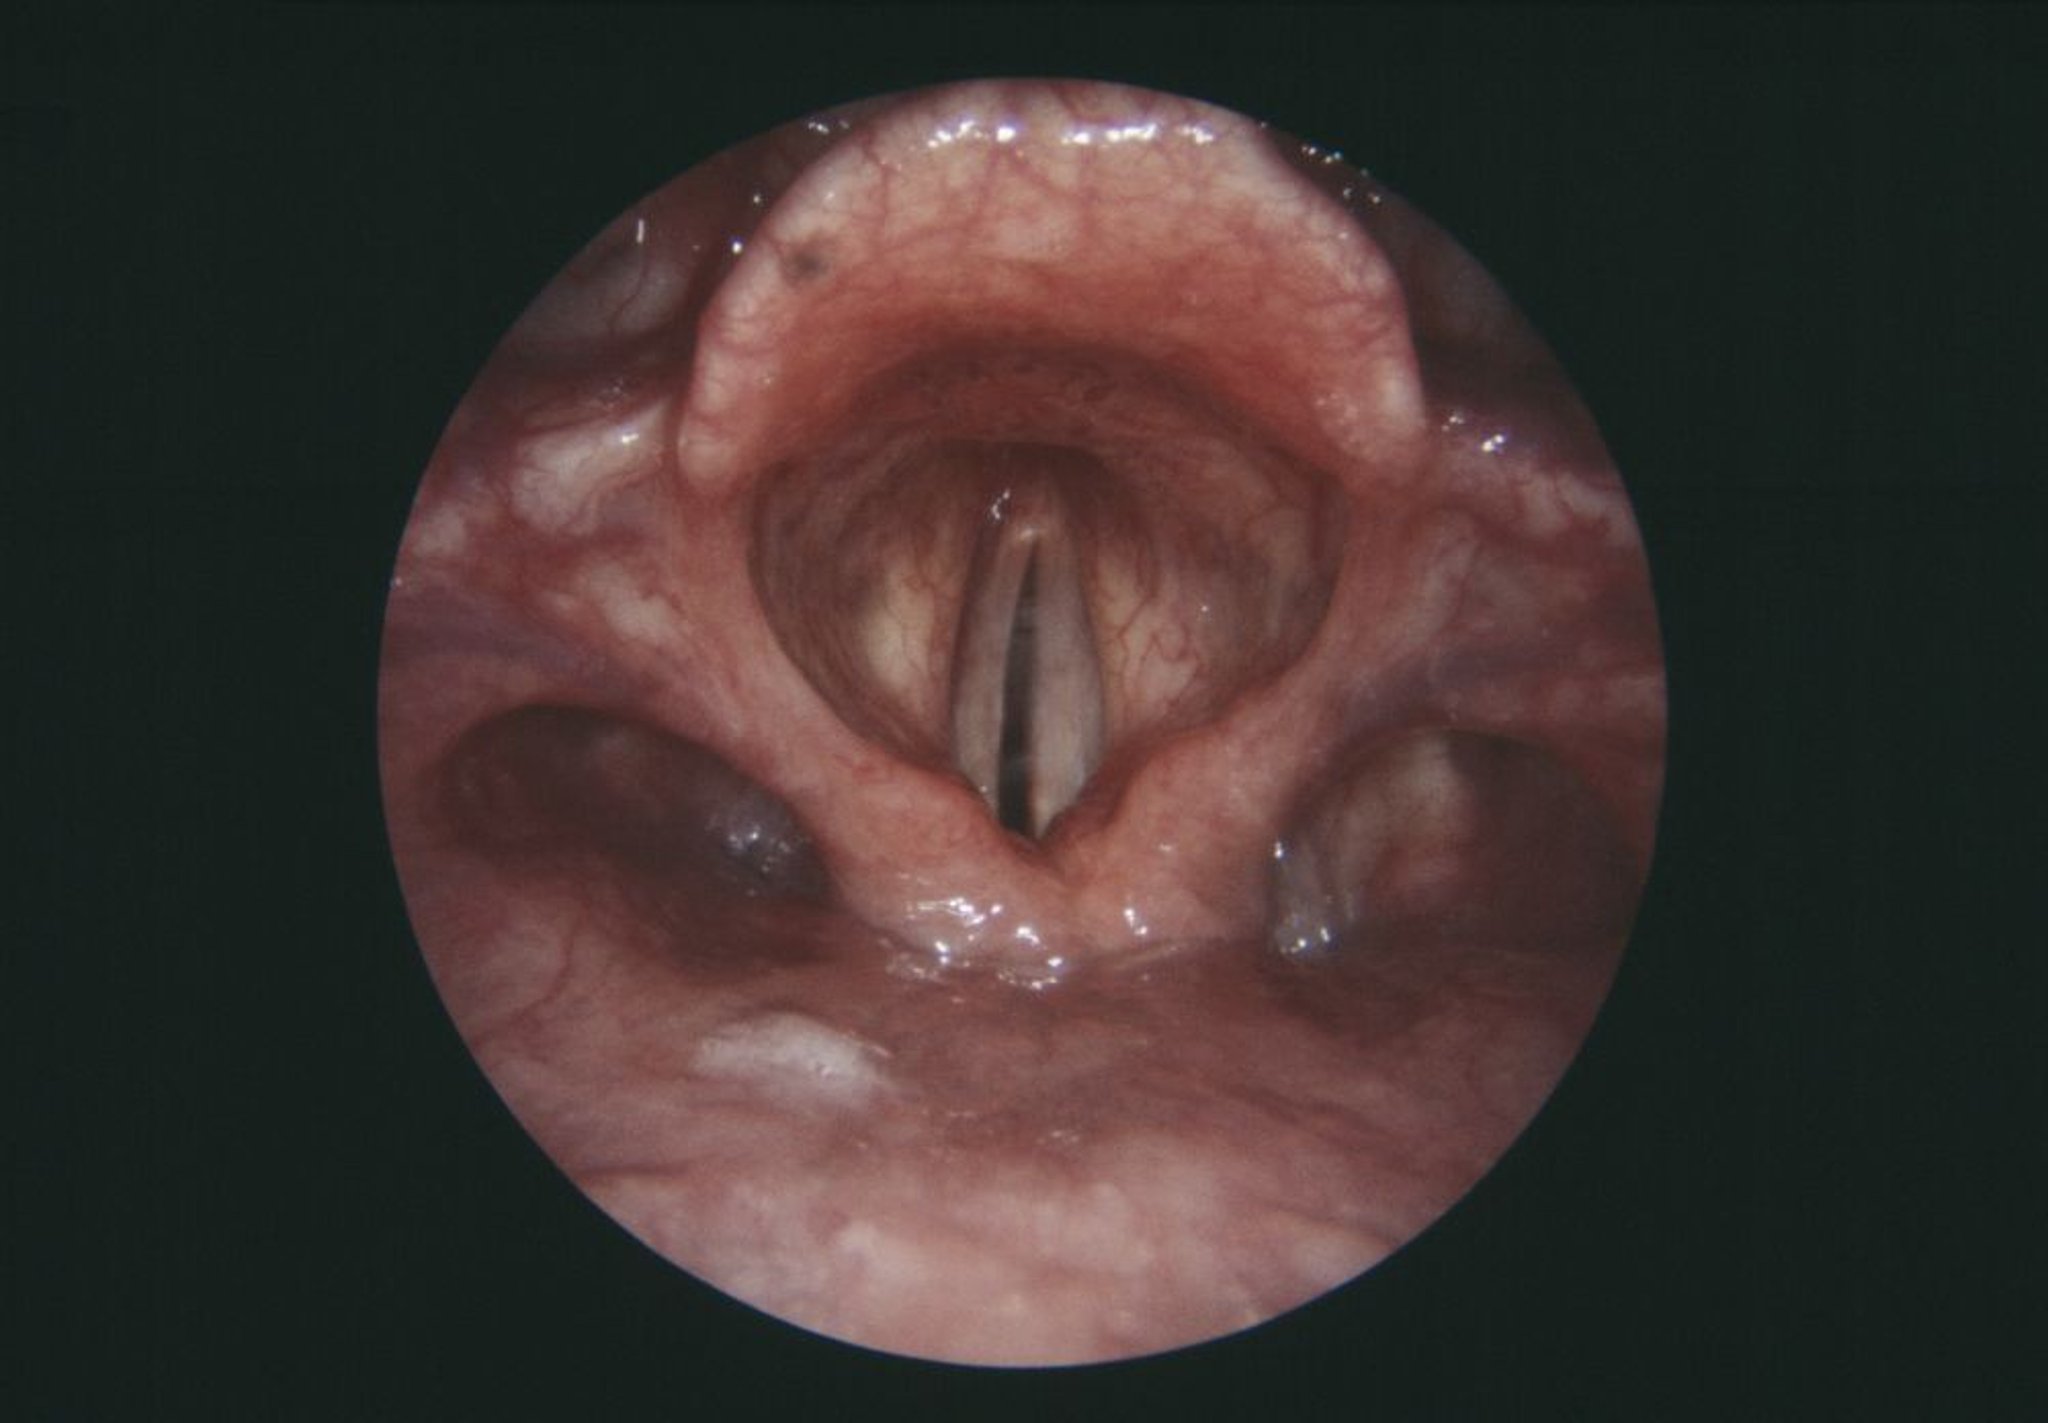

Paralysie des cordes vocales

Cette vue endoscopique du larynx montre une corde vocale droite paralysée (grise, centre gauche).